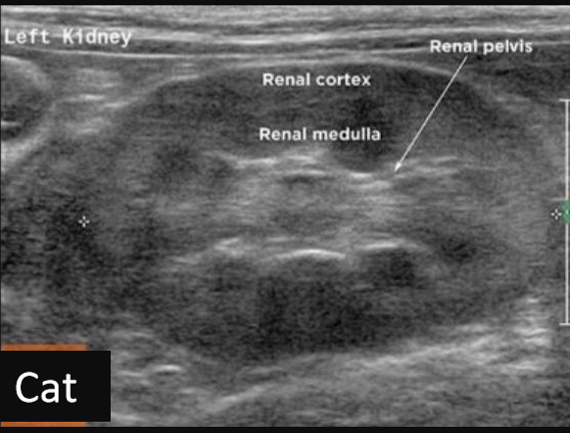

Label this frontal/dorsal kidney ultrasound

Label this frontal/dorsal view kidney ultrasound

Label this sagittal view kidney ultrasound

Label this transverse view kidney ultrasound

Label this ultrasound